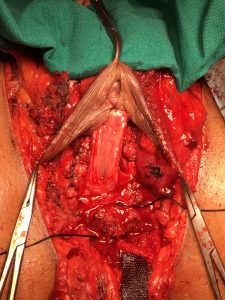

Para tapizar la neo vagina se puede utilizar solo piel del pene en casos muy favorables, o adicionar otras estructuras. La técnica más frecuentemente utilizada agrega un injerto de piel libre escrotal (Figura 3) que luego es modelado sobre un dilatador y que se sutura al cilindro de piel peneana para mayor profundidad. También se puede usar un injerto de piel libre desde otra zona dadora (generalmente inguinal o hipogástrica) o flaps de peritoneo disecados de forma robótica.

En la técnica desarrollada por Dr. Guillermo Mac Millan, se utiliza un colgajo perineal de irrigación inferior además del escroto tratado como injerto libre (Figura 4). Otra alternativa para recubrir el canal vaginal, especialmente en cirugías de revisión y/o en personas trans que, producto de un bloqueo hormonal precoz presenten mínimo desarrollo de estructuras genitales masculinas, es el uso de algún segmento intestinal, principalmente colon sigmoides. Las ventajas de este último es el aspecto mucoso, la lubricación y la posibilidad de alcanzar mayor profundidad. Las desventajas son posible secreción de mal olor y el riesgo propio de una anastomosis intestinal.